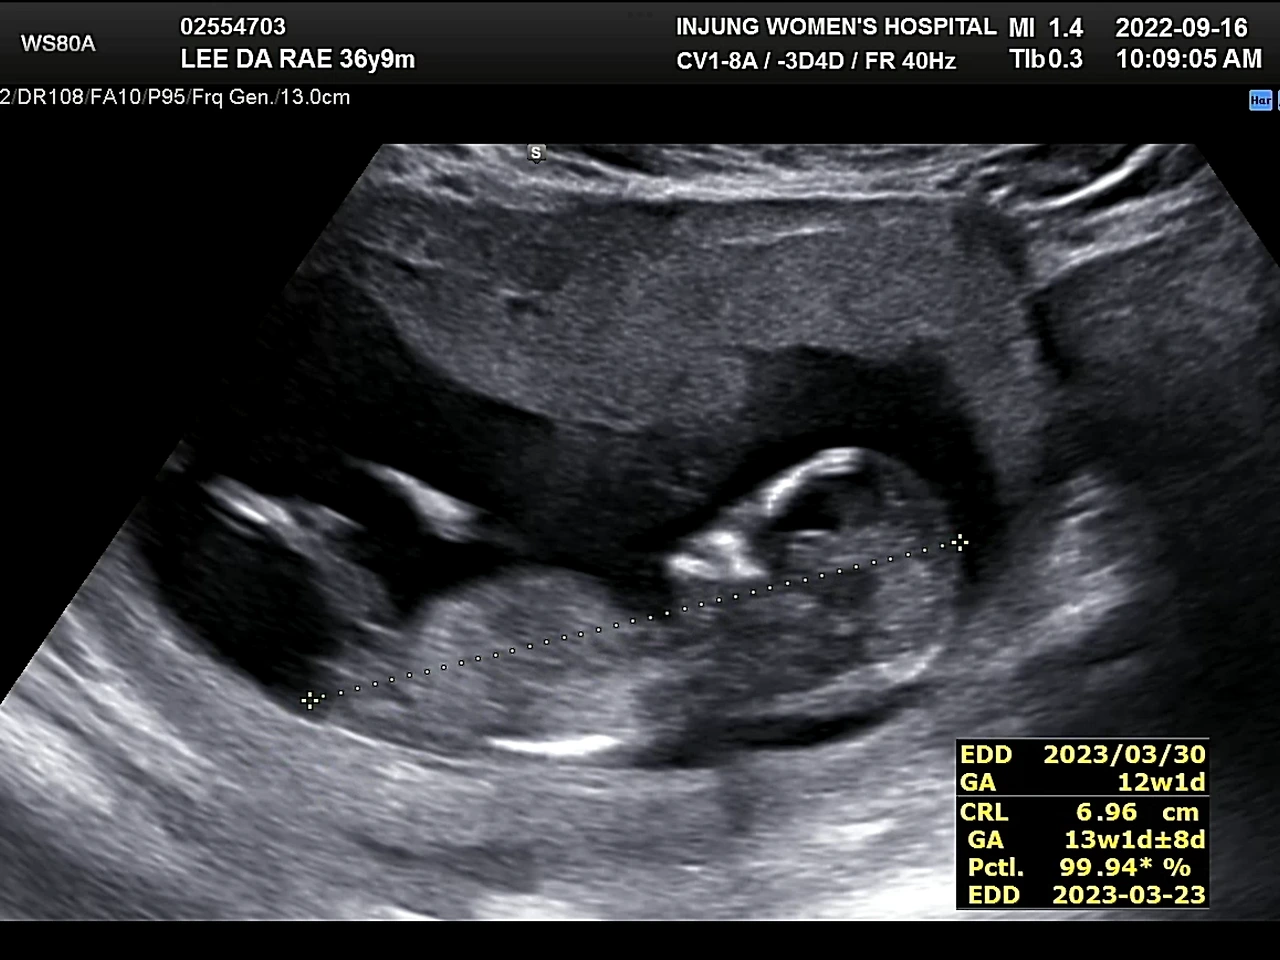

사람들이 안정기라고 부르는 12주에 들어섰다. 이때까지만 해도 병원에 가는 일이 무서웠다. 혹시나 아이가 잘못됐을까 싶은 마음이 컸기 때문이다. 제일 떨리는 순간은 초음파 화면이 흔들리면서 뱃속의 아이를 찾아 헤매다가 무언가 선명하게 보일 때. 이번엔 잘 모르는 내가 봐도 아이가 지난번보다 자라 있는 것 같아서 마음이 놓였다. 그다음 의사 선생님의 “아이가 많이 컸네요.”와 같은 멘트가 이어지고 심장소리를 들었다. 처음 아이의 심장소리를 들을 때보다 이때 들은 심장소리가 더 감동적이었다. 정밀초음파를 끝내고 1차 기형아 검사를 받으러 이동하는 길. 엘리베이터에서 나도 모르게 눈물이 났다. 유산의 두려움에서 어느 정도 벗어났기 때문만은 아니었다. 고작 12주인데, 아이에 대한 내 마음이 너무나 커져버렸다.